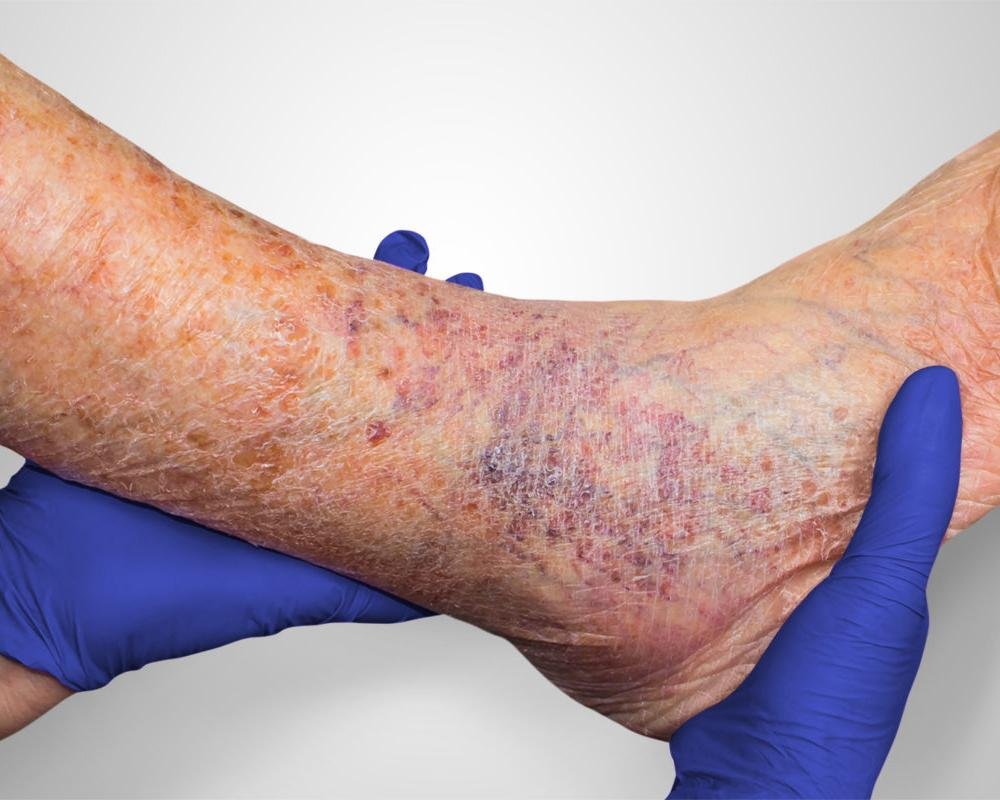

A vascular wound that develops due to poor blood circulation, often in the lower legs and feet. When blood flow is restricted, tissues don’t receive enough oxygen, preventing proper healing. Venous wound, the most common type of vascular wound, result from circulatory problems that cause blood to pool in the veins. Symptoms include skin changes such as thinning, itching, or discoloration, as well as pain, swelling, and a foul-smelling discharge. These wounds may form after minor injuries or due to weakened skin from high vein pressure.

The most common type, often occurring around the ankle or “gaiter area” of the calf. They are caused by sustained high pressure in the veins (venous hypertension), which can lead to pooling blood, swelling, and skin changes.